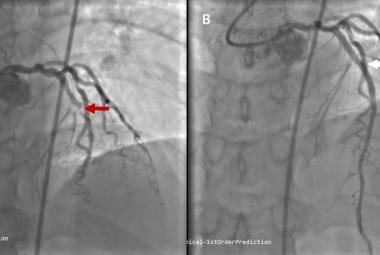

Early Recognition and Intervention of De Winter Syndrome: A Case Report